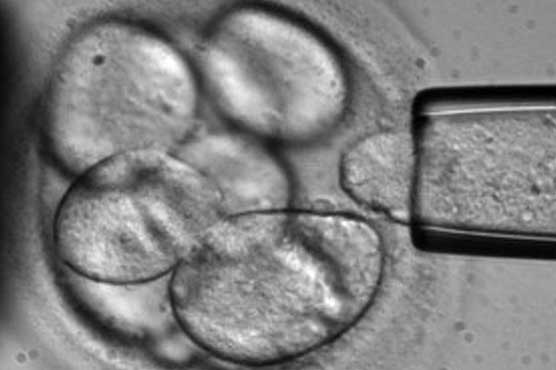

Researchers presented evidence Wednesday for the existence of cancer stem cells, with three different studies seeking to end a decades-old scientific dispute about how tumours grow.The discovery should lead to new drugs targeting stem cells that cause tumours to reappear after cancer therapy, the teams argued in three scientific papers published simultaneously in the journals Nature and Science.The hypothesis (that cancer stem cells exist) has been around now for some time. Hopefully these three papers now make an end to the discussion, Dutch researcher Hugo Snippert told AFP.All the studies were conducted on lab mice.Some experts have maintained that tumours are comprised of masses of cancer cells that are all the same, and all dividing.But Snippert said the latest papers clearly show a hierarchy of cells in tumours, with different functions -- including stem cells that act as cancer cell factories.Stem cells are infant cells that develop into specialised tissues of the body, touted by medicine as a future source from which to replenish damaged tissue.In the case of intestinal cancer, a healthy stem cell mutates to create a cell of origin from which a tumour grows, said Snippert. The tumour contains stem cells which then create new cancer cells.Cancer stem cells must now be targeted for drug research, argued Snippert, a member of the University Medical Center Utrecht research team which focused on intestinal cancer and published its findings in Science.Since the cancer stem cells are so similar to normal stem cells, most treatments also harm the normal stem cells, he said.That is why it is important now to have a look at cancer stem cells, comparing them to normal stem cells to find the differences.Focusing on incurable brain tumours, a US-based research team said they had found a subset of cells that appear to be the source of new tumour growth after chemotherapy.This study serves as a proof of principle that in at least some solid tumours functional cancer stem cells exist, researcher Luis Parada of the University of Texas Southwestern Medical Center told AFP.Also writing in Nature, a separate team in Belgium and the UK found a sub-population of tumour cells with stem-like properties in skin cancer.Taken together these reports provide evidence that point towards the existence of cells that may represent cancer stem cells, said a Nature press statement.Snippert said the latest technology has allowed the scientists to examine tumour cancer growth in as natural a state as possible, unlike earlier studies that involved tumour transplants in lab mice.The Dutch team was able to breed special mice in which different tumour cells displayed different colours which could then be studied under a microscope.Say the tumour cells were red and the stem cell blue, the scientists could follow the stem cells progeny as they spread in the tumour.Because of the colours we could visualise everything within one and the same tumour in its original mouse at the original position where the tumour was formed, Snippert said.It is more natural... as it would behave normally in patients.The three teams studied different organs using somewhat different techniques, but all with technology that allowed them to let the tumours grow undisturbed, said Snippert.Better understanding of the cancer stem cells will be critical for re-evaluation of existing therapies and development of new ones, added Parada.